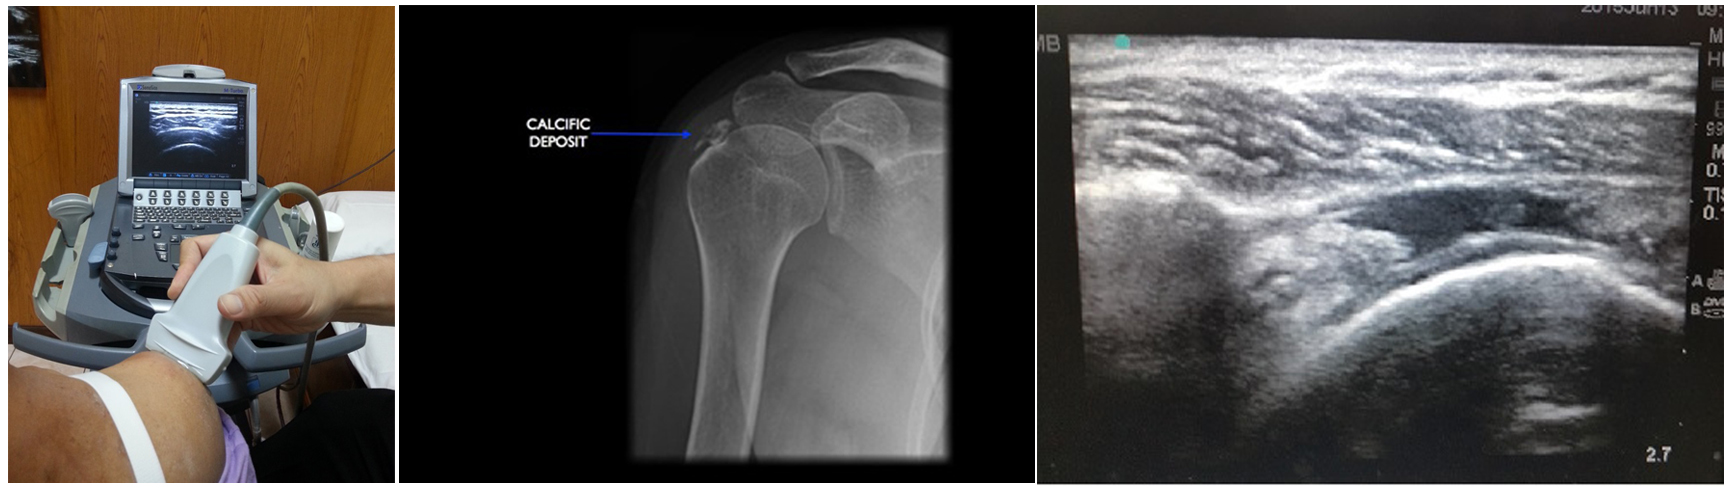

ในปัจจุบันการใช้เครื่องคลื่นเสียงความถี่สูง (Ultrasound) นับว่ามีประโยชน์อย่างมากในการช่วยในการวินิจฉัยและประเมินสภาพของเส้นเอ็นในบริเวณข้อไหล่ ข้อดีของการตรวจด้วยคลื่นเสียงความถี่สูง คือ สามารถตรวจได้ง่ายและได้รับการวินิจฉัยอย่างรวดเร็วจากแพทย์ที่มีประสบการณ์ในการตรวจ ผู้ป่วยไม่ต้องได้รับแสงรังสีซึ่งมีความปลอดภัยต่อผู้ป่วย ราคาไม่แพงมากเหมือนกับการตรวจด้วยเครื่องแม่เหล็กไฟฟ้า (MRI) การตรวจด้วยคลื่นเสียงความถี่สูงจะสามารถทำให้แพทย์มองเห็นว่าเส้นเอ็นมีการบวม การอักเสบ การฉีกขาด หรือในบางครั้งที่มีหินปูนเกาะที่เส้นเอ็น ซึ่งจะทำให้เกิดการอักเสบ ผู้ป่วยมีอาการปวดไหล่มากจนไม่สามารถขยับข้อไหล่ได้ โดยอาการมักจะเป็นแบบเฉียบพลัน การตรวจด้วยคลื่นเสียงความถี่สูงก็จะช่วยให้แพทย์ทำการวินิจฉัยได้อย่างรวดเร็ว

การถ่ายภาพเอกซเรย์จะช่วยประเมินลักษณะของกระดูกบริเวณไหล่ว่ามีการเสื่อมของกระดูกข้อไหล่หรือไม่ รวมทั้งในกรณีที่มีหินปูนไปเกาะที่เส้นเอ็นซึ่งทำให้เกิดการอักเสบก็สามารถเห็นได้จากภาพเอกซเรย์ รวมทั้งประเมินดูว่าลักษณะทั่วไปของกระดูกข้อไหล่ไม่มีการถูกทำลาย ซึ่งอาจจะพบได้บ้างแต่ไม่มากที่กระดูกบริเวณหัวไหล่ เกิดเนื้องอกและมีการทำลายกระดูกบริเวณข้อไหล่และทำให้เกิดอาการปวด